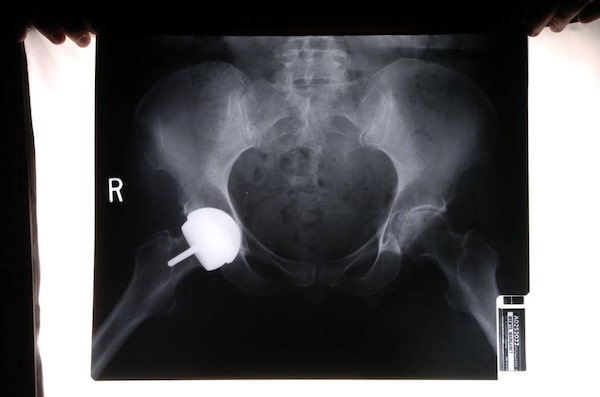

X-rays of Margaret Wente’s right hip replacement.Louie Palu/The Globe and Mail

Eight years ago, I sat in a surgeon's office as he showed me X-rays of my deteriorating hips. He told me they were finished. I was only in my 50s, but I wasn't surprised. By the time I saw him, I could scarcely walk. I had skied and hiked and led a reasonably active life, but now I was a cripple. Sometimes I had to use the railings to drag myself hand over hand up the stairs.

Soon I found some more good news. A top orthopedic surgeon in Montreal was doing a newer procedure called hip resurfacing, specifically targeted at younger, active people. Resurfacing, which is an alternative to total hip replacement, had been popular in Europe for years. The advantage was that, after surgery, you could do everything again. There was also another innovation on the market – all-metal implants that promised to last much longer than the standard metal-and-plastic devices that had been in use for years. My crumbling arthritic joints would be replaced by a shiny ball and socket made of cobalt and chromium – a miracle of medical engineering.

The waiting list in Montreal was short. Within months, I had two new metal hips made by DePuy Orthopaedics Inc., which started out making splints for Indiana farmers in 1895. I even wrote about them in The Globe and Mail. Readers across the country asked for my advice. Many of them wound up getting the same type of implant.